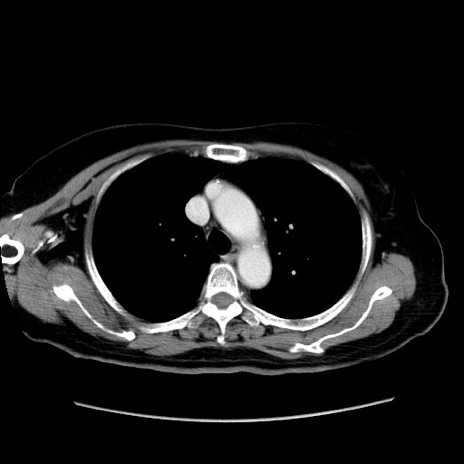

冠状断像

【症例】80歳代女性

【主訴】下腹部痛

【現病歴】約8時間前より下腹部痛の出現あり、救急外来受診。

【既往歴】両側付属器切除

【身体所見】意識清明、下腹部正中に手術痕あり、その部位に一致して圧痛と反跳痛あり。腸蠕動音は亢進。

【データ】WBC 9300、CRP 0.15